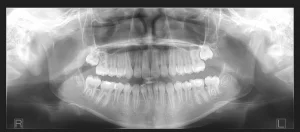

Here is a section from a typical panoramic radiograph. In it, because of the reasons we just discussed, we can see that the image does not show the apices of the maxillary anteriors very clearly.

If this was taken with a panoramic x-ray that cannot capture multiple focal troughs, then the office is stuck with this image.